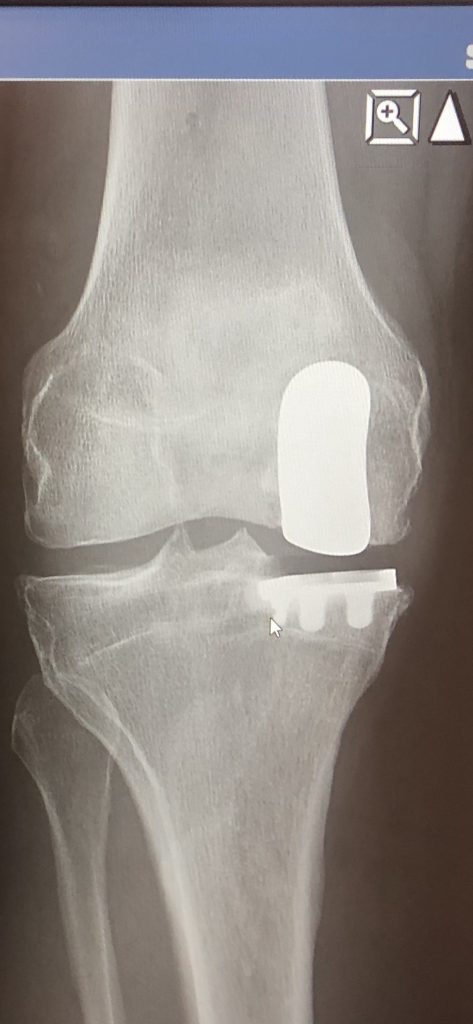

Instead of replacing my whole knee, Dr. Nawabi was able to save 2/3's of my knee. 6 months after surgery I have very little pain and enjoy an active lifestyle. I have provided pictures of my bone on bone knee prior to surgery and the partial knee replacement 6 months after surgery. I even hiked in the Rocky Mountain National Park just 10 weeks after surgery.